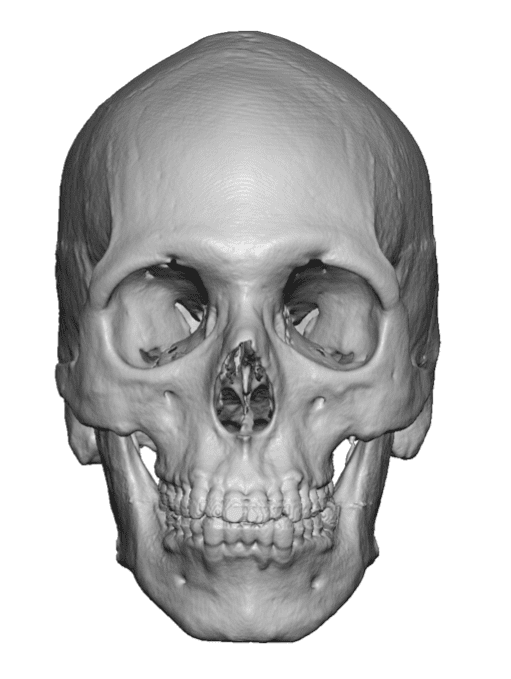

Severe narrowing skull deformity from prior sagittal craniosynostosis repair as an adult.

Complete replacement of entire skull by a custom implant with temporal fat injections.